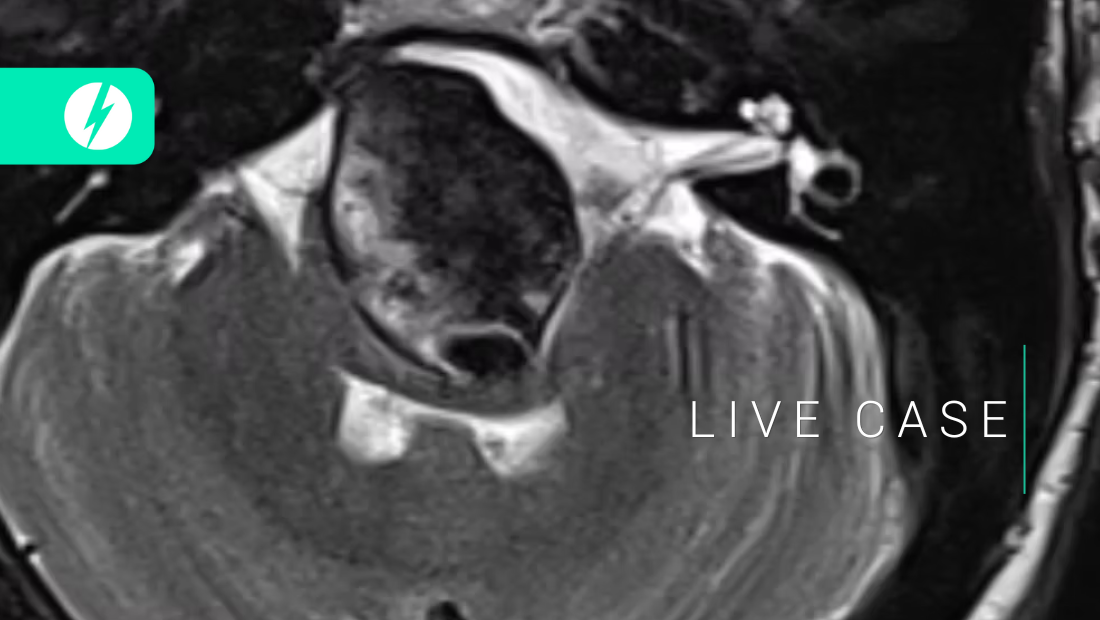

Ruptured aneurysm: Complex ruptured MCA aneurysm - Ep.1/2